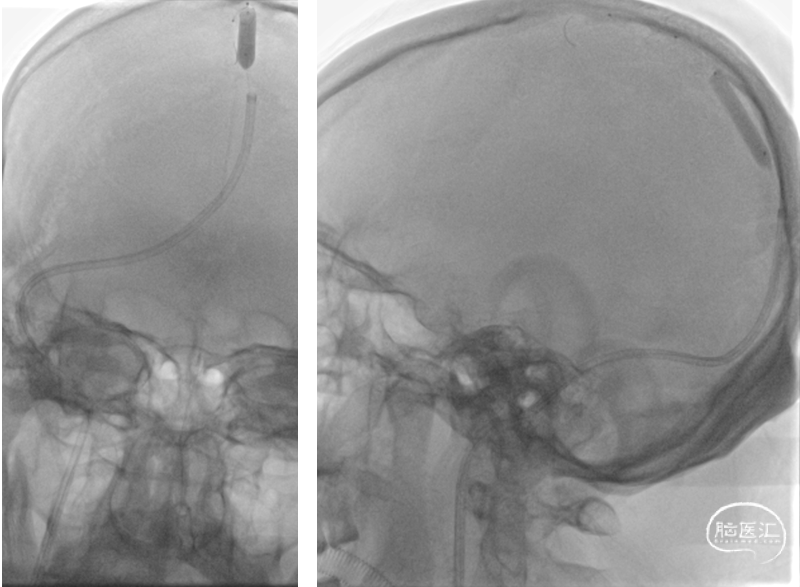

复查造影上矢状窦显影好转,静脉回流较前改善,右侧横窦及乙状窦仍显影欠佳

复查造影右侧横窦显影良好,静脉回流明显改善,乙状窦显影仍欠佳

复查造影:上矢状窦显影明显改善,右侧横窦及乙状窦显影良好,静脉回流良好

颅内正侧位造影:上矢状窦显影明显改善,右侧横窦及乙状窦显影良好,静脉回流良好